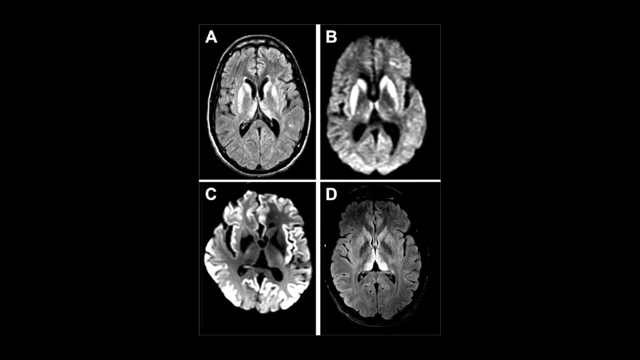

Manyetik Rezonans Görüntüleme (MRI): Hastalığa %90 oranında teşhis konulmasında etkilidir.

Beyin Omurilik Sıvısı (BOS) Analizi: BOS testi ile daha kesin sonuçlara ulaşılabilir.

Elektroensefalografi (EEG): Beyindeki elektriksel anormallikleri gösterir.